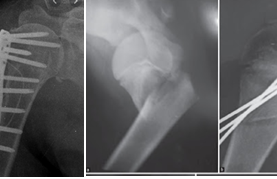

Co rút Dupuytren là bệnh gây ra các nốt sần, cục u hoặc bướu nhỏ dưới da ngón tay và lòng bàn tay, thường ảnh hưởng tới các ngón thứ tư và thứ năm. Bệnh nhân có thể thấy cảm giác bó chặt các ngón bị bệnh đến nỗi khó duỗi, đôi khi có tăng cảm giác đau. Một số trường hợp, sự co thắt này làm ảnh hưởng nặng đến chức năng và vấn đề thẩm mĩ, song hầu hết bệnh nhân chịu đựng tốt bởi vì sự co thắt xuất hiện ở trạng thái chức năng bình thường của bàn tay.